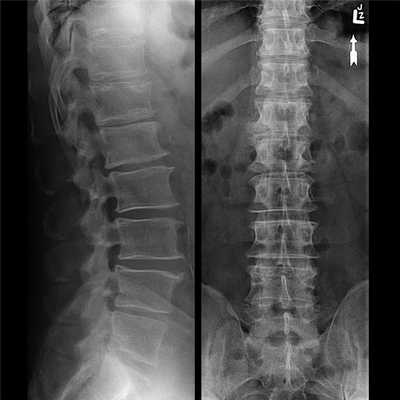

Диагноз может быть выставлен на первом приеме у невролога или вертебролога на основании жалоб пациента, данных анамнеза, внешнего осмотра. Для его подтверждения проводится ряд инструментальных исследований:

- рентгенография. Наиболее информативна при шейно-грудном остеохондрозе. На полученных изображениях заметны деформированные позвонки, уменьшение промежутков между ними, образовавшиеся костные наросты;

- МРТ или КТ. Проведение исследований позволяет обнаружить изменения межпозвонковых дисков, оценить состояние связок, мышц, кровеносных сосудов, спинномозговых корешков.